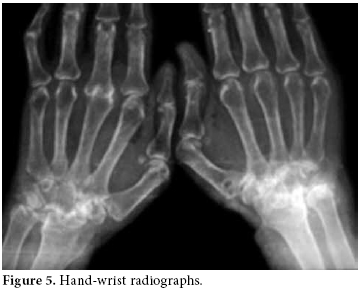

A chest radiograph showed an increased cardiothoracic index and medium to severe bilateral pleural effusion which was more pronounced in the posteroanterior right lung (figure 1).

Pulmonary X-rays showed moderate and severe bilateral pleural effusion, more pronounced in the right lung, and an increased cardiothoracic index.